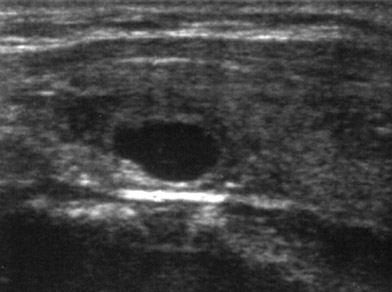

L'ecografia della tiroide è un'indagine di approfondimento diagnostico nel campo della fisio-patologia della tiroide, la quale utilizza gli ultrasuoni trasmessi da una sonda piana alla frequenza compresa tra 7,5 e 13 MHz. Una piccola sonda invia e riceve ultrasuoni (suoni ad altissima frequenza che non possono essere uditi dall'orecchio umano) che vengono riflessi in misura diversa dalle strutture del corpo; viene appoggiata sul collo dopo avervi deposto una piccola quantità di gel conduttore. L'immagine viene catturata ed elaborata da un computer che la registrata come una fotografia.